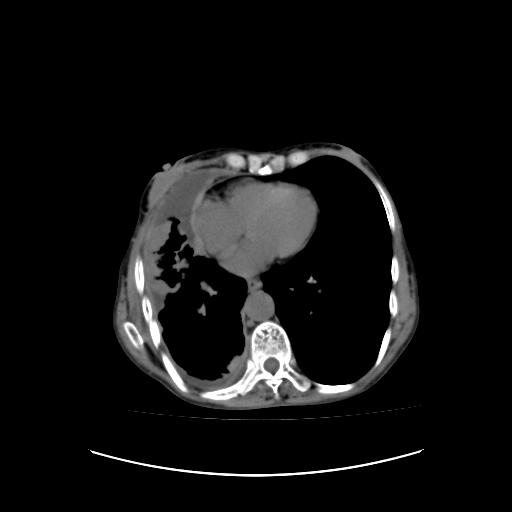

标题: CT16930:女 59 胸痛6个月 胸水脱落细胞学见瘤细胞 [打印本页]

标题: CT16930:女 59 胸痛6个月 胸水脱落细胞学见瘤细胞

右侧胸廓塌陷,右侧胸膜广泛增厚并见多发胸膜结节,右侧少量胸腔积液并包裹。

右侧胸膜转移瘤,原发灶可能就在在右肺,另外建议检查右侧乳腺.

胸膜转移瘤  包裹性胸腔积液  肺内转移

右胸腔结节均考虑来自胸膜(部分来源于叶裂),考虑胸膜间皮瘤或转移瘤.